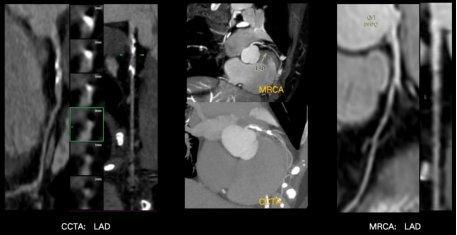

但是到目前为止,冠脉的磁共振成像,一直是临床上的一个技术挑战。因为冠脉走形迂曲,结构细小,受心脏搏动及呼吸影响较大,容易扫描失败率高、扫描时间长、图像不佳,因此在临床很难常规开展。但是基于飞利浦的无液氦2.0双芯磁共振,通过极致均匀的无液氦磁体以及魔方平台的强强硬件组合,大幅改善了冠脉扫描的成功率,极大地提升了扫描速度,并且保证了较好的图像质量。目前无液氦2.0双芯磁共振,可以在无需注射对比剂的前提下,无创、无辐射的带来媲美金标准CTA的检查效果。甚至CTA在遇到钙化斑块时,伪影影响可能过高评估狭窄程度,从而导致狭窄评估可能偏差,但双芯磁共振的冠脉检查能够清晰显示冠脉管腔结构,无伪影影响,狭窄评估更准确。